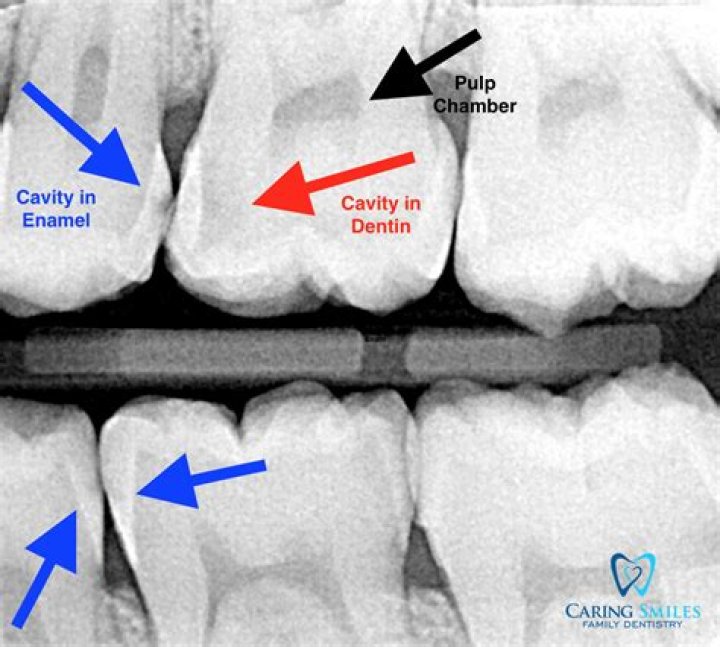

How long does it take to fill 3 cavities?

However, the length of the procedure will vary depending on the size and location of the cavity, which can take anywhere from 10 minutes to an hour. In cases of minor to moderate decay or chipping on one, two, or three surfaces, a filling is a common dental procedure.